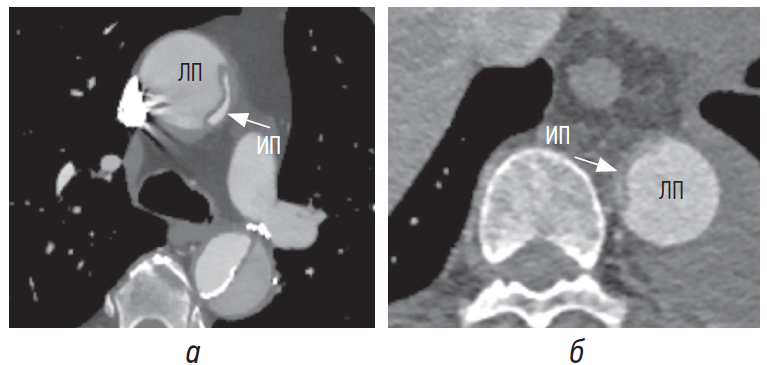

При диссекции аорты давление в ложном просвете превышает или равно давлению в истинном просвете, что приводит к сдавлению последнего (рис. 1, а) вплоть до его коллапса (рис. 1, б) [1, 4, 8].

Рис. 1. Сдавление истинного просвета в восходящем отделе аорты, коллапс истинного просвета в нисходящем отделе аорты. ИП — истинный просвет, ЛП — ложный просвет

Расширение ложного просвета происходит из-за снижения эластичности его тонкой стенки, содержащей только около 1/3 от исходного количества эластина в сравнении с истинным просветом. В конечном итоге натяжение тонкой стенки ложного просвета может приводить к формированию псевдоаневризмы и разрыву ложного просвета. Общая степень дилатации зависит от артериального давления, остаточной толщины стенки и процента окружности стенки, вовлеченного в расслоение [4]. Больший размер является значимым маркером ложного просвета как при острой, так и при хронической диссекции (рис. 2, а, б) [8].

Рис. 2. Ложный просвет больше истинного просвета при острой диссекции (а) и при контроле через 1 год (б). ИП — истинный просвет, ЛП — ложный просвет

Соотношение размеров истинного и ложного просветов при хронической диссекции больше по сравнению с их соотношением при острой диссекции (рис. 3, а, б) вследствие относительно стабильного размера истинного просвета в сочетании с формированием дегенеративной псевдоаневризмы ложного просвета. Разница наиболее значительна дистальнее отхождения левой подключичной артерии и выше уровня отхождения чревного ствола [7]. При этом истинный просвет чаще имеет цилиндрическую или нитевидную форму.

Рис. 3. Отношение размеров истинного и ложного просветов в острый период (а), в хронический период через 1 год (б). ИП — истинный просвет, ЛП — ложный просвет